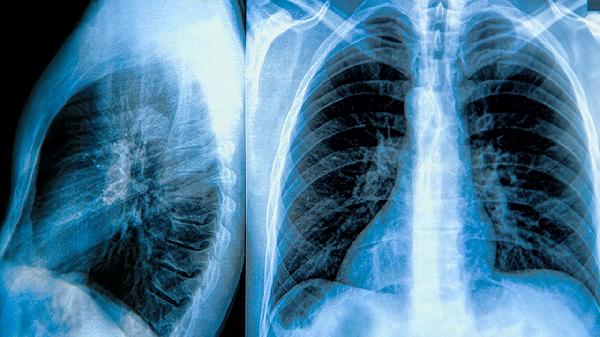

慢性阻塞性肺疾病(COPD)的急性加重期患者的预期寿命因个体差异而异,通常在数月至数年之间。影响预期寿命的主要因素包括患者的整体健康状况和病情的严重程度。对于一些病情较轻、身体状况较好的患者,通过及时的治疗和管理,可以有效控制病情,减少急性加重的发生,从而延长寿命。

1、病情严重程度:慢性肺阻塞性疾病急性加重是指因为感染或其他因素导致的肺部症状突然加重。病情较轻的患者,若能得到及时的治疗,如使用抗生素、支气管扩张剂等,通常可以有效控制病情。这些措施有助于减少急性加重的次数,进而延长患者的寿命。然而,对于那些病情严重的患者,例如存在严重的呼吸功能衰竭或肺动脉高压,可能会出现持续的呼吸困难和活动受限,甚至需要长期的氧疗或机械通气支持,这些因素可能会缩短患者的预期寿命。